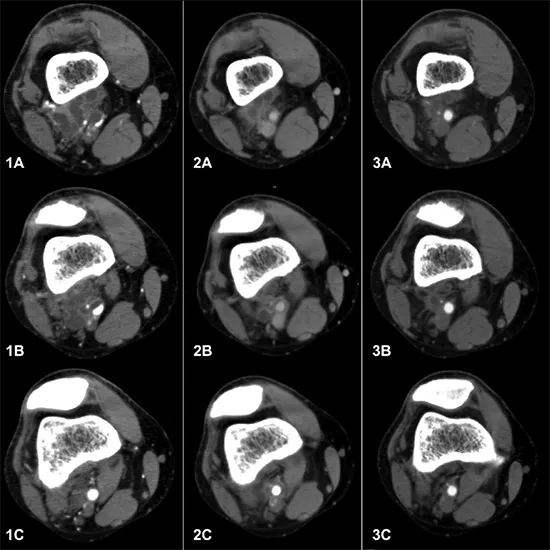

CECT (Contrast Enhanced Computed Tomography) Left Ankle Joint is a diagnostic imaging procedure used to identify problems with the left ankle joint. If a fracture, injury, infection, inflammation, or other disorder is not visible on the X-ray, the doctor may recommend this scan to evaluate the left ankle joint regions for fracture, injury, infection, inflammation, or other disorders. The radiologist will inject you with contrast media and take images of your left ankle joint with a rotating x-ray beam.

This test is used to detect ankle joint bone fractures that are not visible on a simple X-ray.